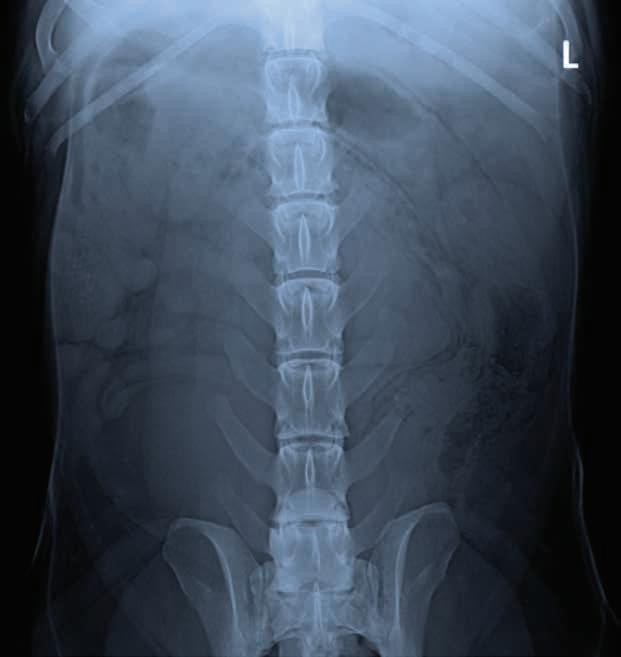

A 3-year-old, male neutered Labrador Retriever presented for chronic diarrhoea. t he patient had a history of inflammatory bowel disease and had undergone multiple previous surgeries for foreign body removal. A colopexy had also been previously performed. t he patient had completed a course of metronidazole on the day of presentation and was also receiving vitamin B12, psyllium husk (metamucil) and probiotics. He was up to date with de-worming treatment and core vaccinations. A three-view abdominal radiograph series was taken as part of the diagnostic workup, and two cropped projections are provided below (Figure 1).

Figure 1. l eft lateral (a) and ventrodorsal (b) abdonimal radiographics of a dog with chronic diarrhoea.

a b